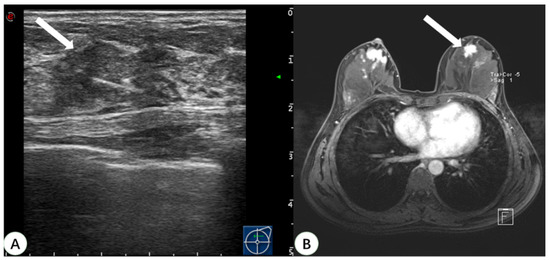

Pathologic confirmation was eventually obtained for 31 lesions. A total of 22 of the lesions were surgically resected, and post-procedural MRI showed that the lesions disappeared. Nine lesions had US-guided biopsy performed only, and the pathological findings were benign, with no change in the lesions on follow-up MRI for two years. The pathological types of these 31 lesions detected by real-time US with MRI virtual navigation are shown in Table 2. Among them, 87.1% (27 cases) were benign lesions (18 were adenosis, 5 intraductal papilloma, 2 fibroadenoma, and 2 atypical hyperplasia), and 12.9% (four cases) were malignant lesions. The pathological type of all malignant lesions was ductal carcinoma in situ (DCIS). Two of the malignant lesions were multifocal lesions in the unilateral breast of the same patient. The pathology showed that the maximum diameter was 0.6 cm and 0.5 cm, respectively. One malignant lesion was a widespread hypoechoic area, which was pathologically demonstrated as DCIS with a maximum diameter of 3.0 cm. Another malignant lesion was a wide-ranging lesion of the bilateral breast in the same patient and the lesion in the left breast was located with real-time US with MRI virtual navigation (Figure 4). The pathological type was DCIS with a maximum diameter of 1.4 cm in the left breast and 2.0 cm in the right breast. All malignant lesions underwent radical resection, and the final histopathological diagnosis was the same as before. These four malignant lesions were all non-mass enhancements on MRI.

Figure 4.

A 46-year-old woman with dense breast tissue underwent virtual navigation: (A) Real-time US with virtual navigation detected the corresponding lesion (arrow) in the left breast at the 12-o’clock position 2 cm from the nipple, which underwent ultrasound-guided biopsy; (B) CE-MRI showed a suspicious enhanced irregular lesion (arrow) in the upper left breast, undetected at second-look US. Pathology obtained by US-guided biopsy with virtual navigation demonstrated a ductal carcinoma in situ. US = ultrasound; CE-MRI = contrast-enhanced magnetic resonance imaging.